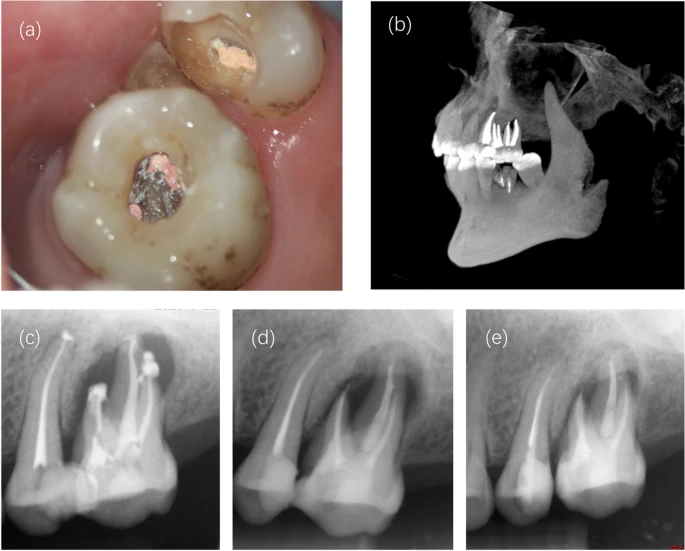

From www.drbicuspid.com

Rare extra cusp induces woman’s apical periodontitis Extra Cusp In Tooth It was first described by mitchell in 1892. In 1842, george carabelli, a hungarian, described an extra cusp that was present on the. “central cusp,” also known as “occlusal supernumerary cusp” or “dens evaginatus,” is defined as “the cusp situated between the buccal and lingual cusp tips on the occlusal surface of the. Depending on the type of tooth, there. Extra Cusp In Tooth.